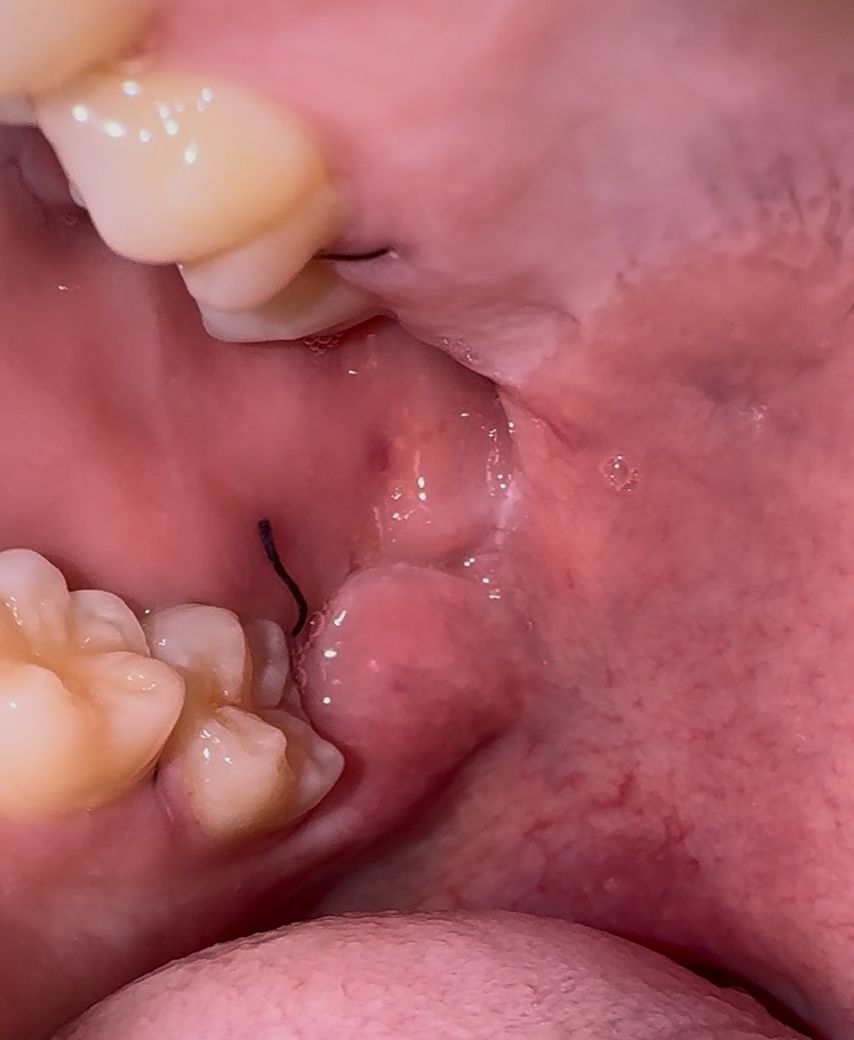

사랑니 1일차입니다 상태 어떤거같나요?

13일 오후에 아래 수평매복사랑니하고 위 매복사랑니 발치하고 난 뒤 오늘 상태입니다. 크게 통증은 안느껴지는데 상태 어떤거같나요?

사진상으로 크게 문제가 되어 보이는건 없는거 같습니다. 자극만 가지 않도록 해주시면될것같습니다.

사진으로 봤을 경우에는 봉합이 잘 되어있고 문제가 없는 것으로 보입니다. 발치를 했다면 발치한 부위가 자극이 되지 않도록 하는 것이 좋습니다. 발치한 부위가 자극이 되면 출혈이 되고 치유가 늦어질 수 있기 때문입니다.

붓기는 조금 있어보이나 염증 등의 문제는 보이지 않습니다. 시간이 지나면 잘 나을 것 같습니다.